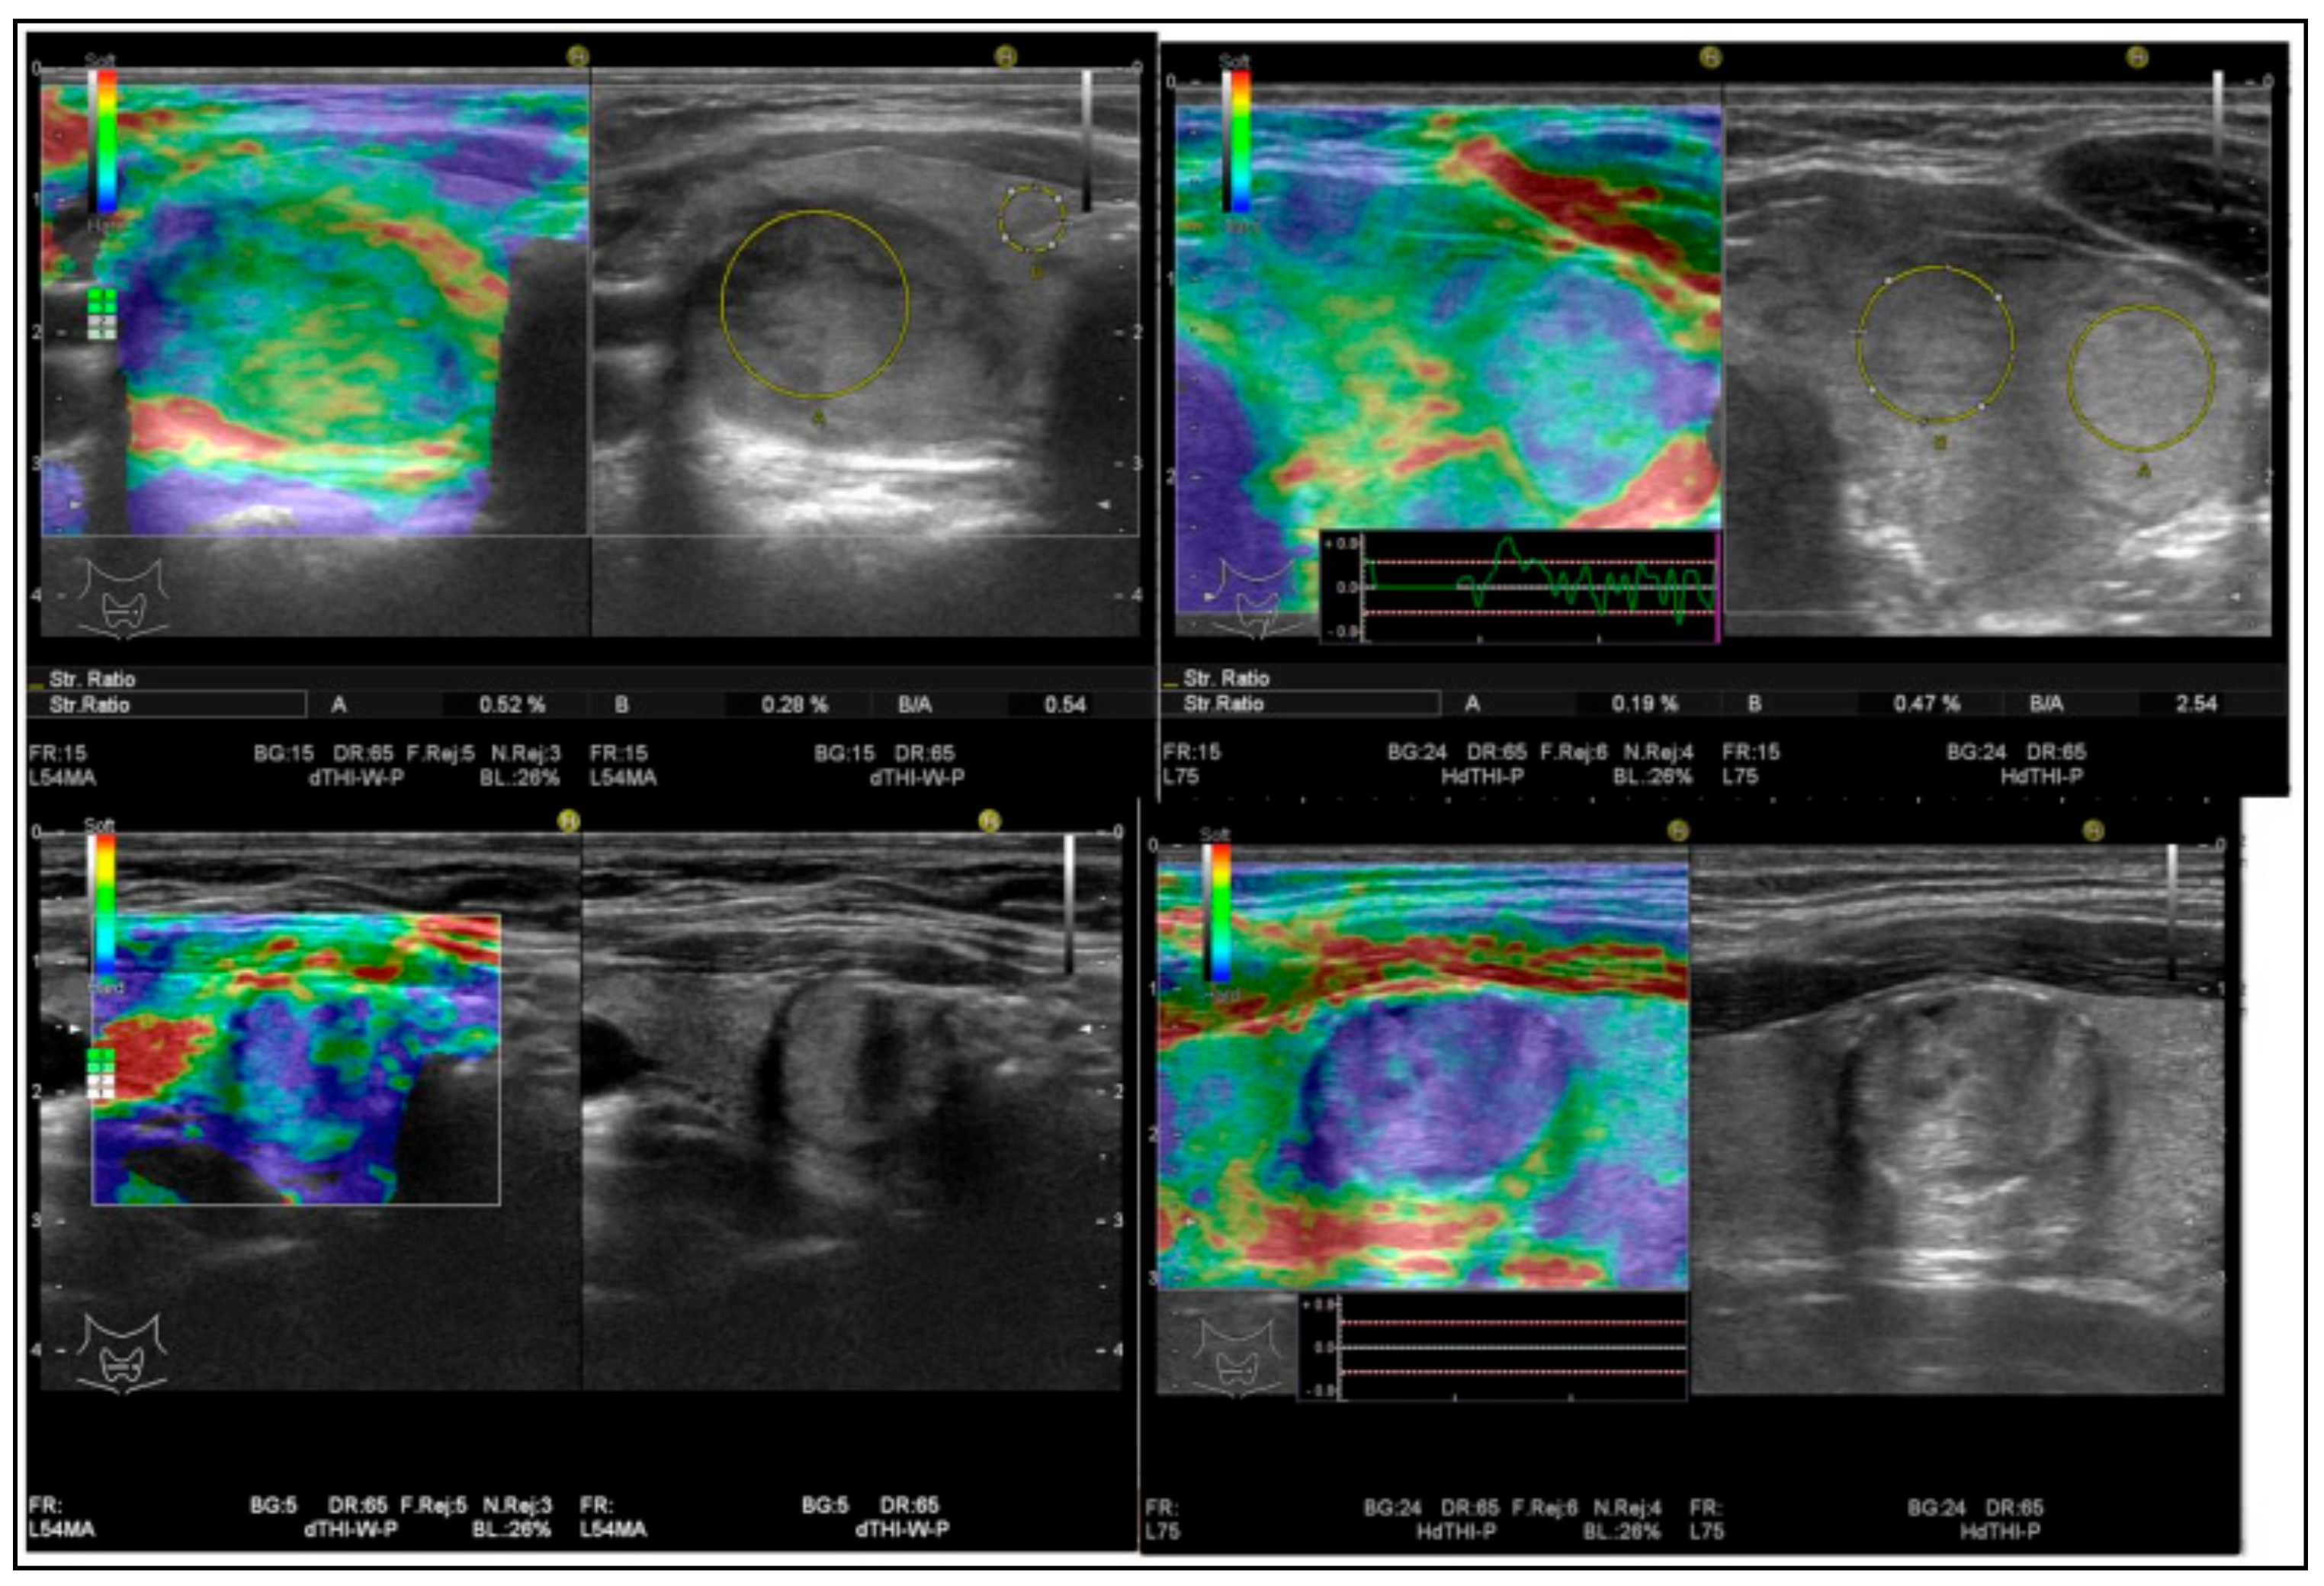

- Stoian, D.; Timar, B.; Derban, M.; Pantea, S.; Varcus, F.; Craina, M.; Craciunescu, M. Thyroid Imaging Reporting and Data System (TI-RADS): The impact of Quantitative Strain Elastography for better stratification of cancer risks. Med. Ultrason. 2015, 17, 327–332. [Google Scholar] [CrossRef] [PubMed]